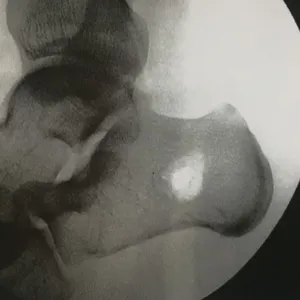

Intraop Pics Of Plantar Medial Foot Release for Chronic Exertional Compartment Syndrome in the foot